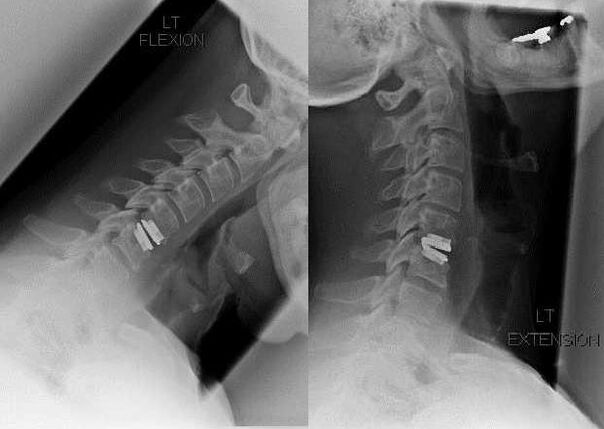

- crunching, clicking when tilting or turning the head;

- limited mobility in the cervical spine;

As the intervertebral discs and vertebrae deform, the patient's condition worsens.The course of osteochondrosis is complicated by neurogenic symptoms caused by compression by osteophytes or hernial protrusion of the spinal roots and vertebral artery.Headache, dizziness, changes in blood pressure appear, visual and hearing acuity decrease.